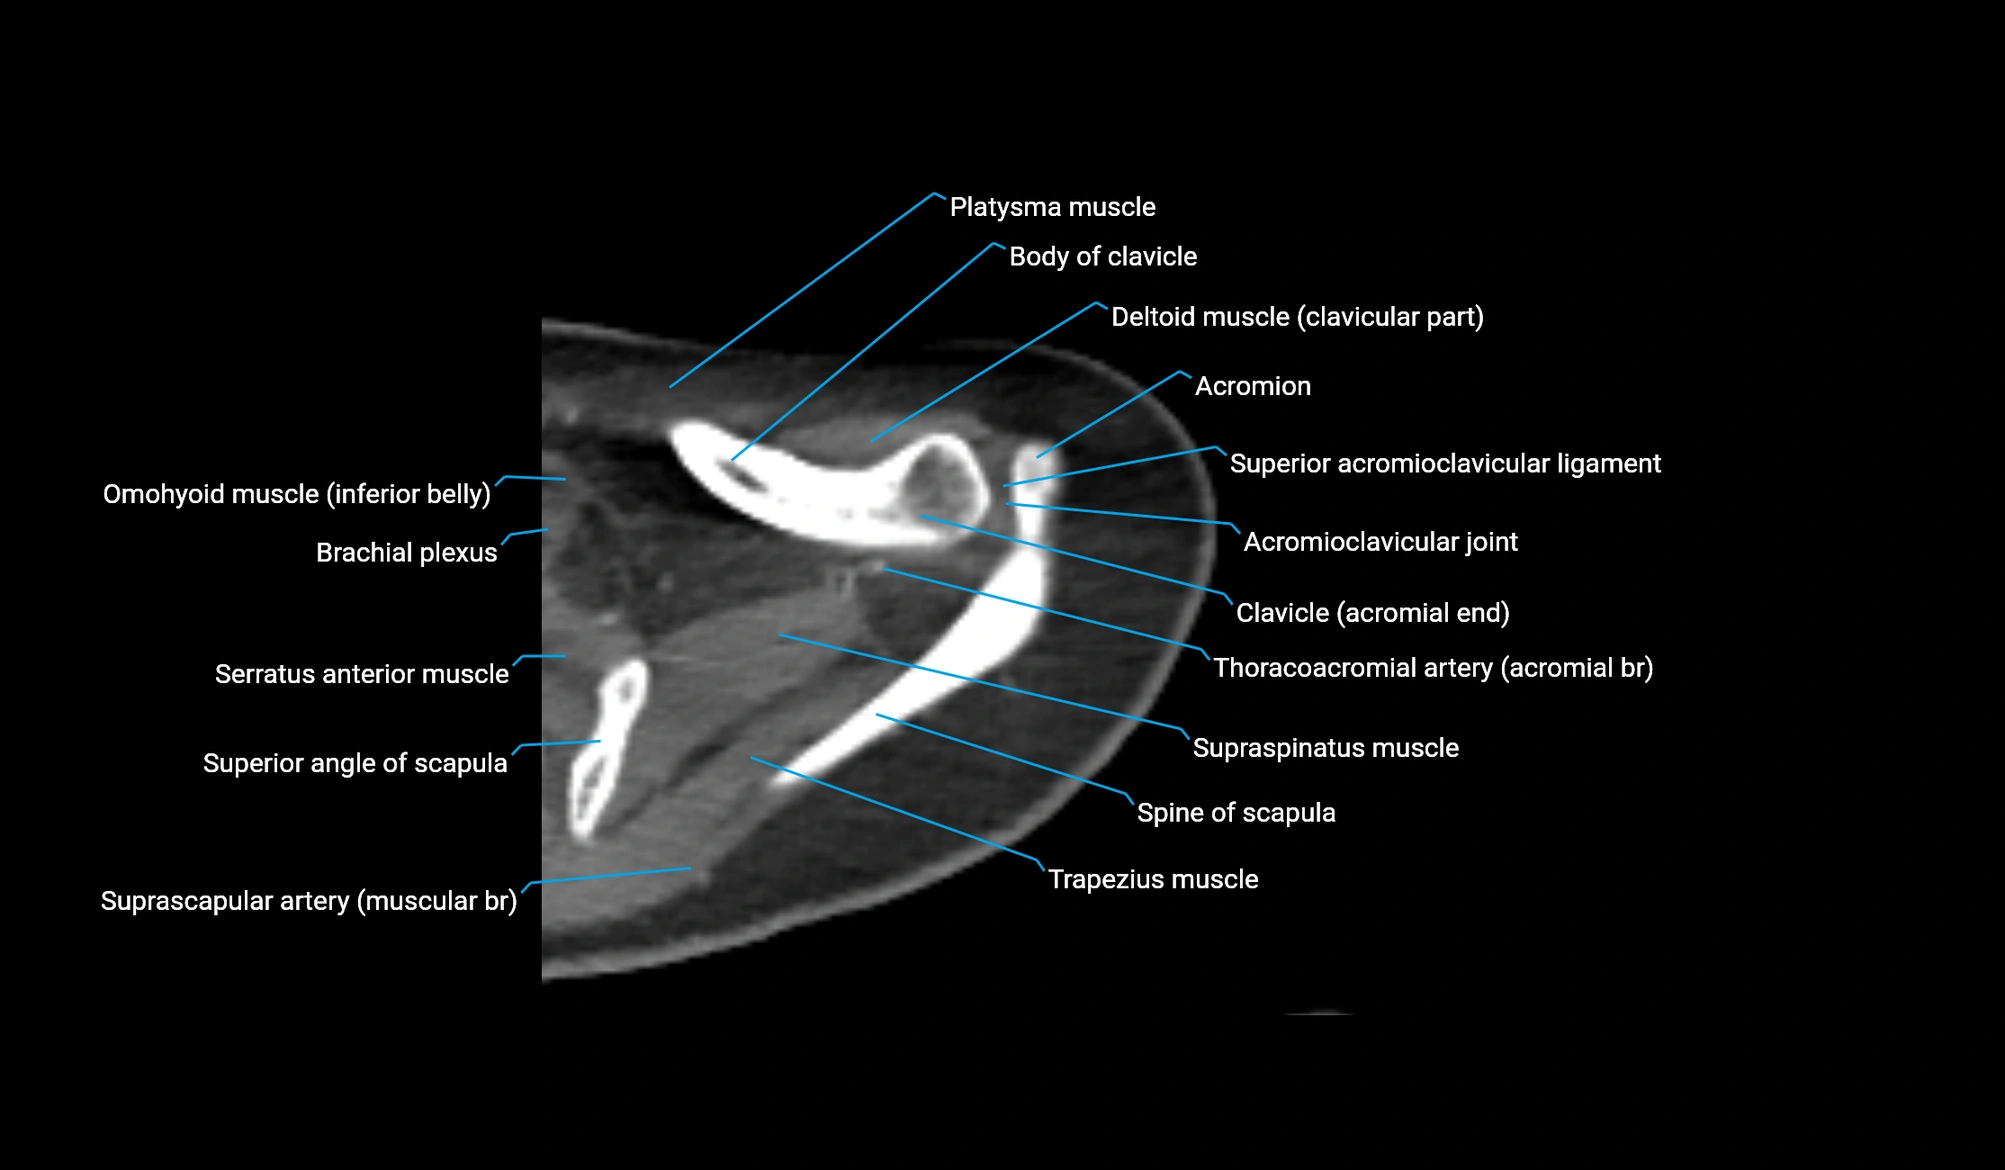

- Acromial end of clavicle

- Acromioclavicular joint

- Acromioclavicular ligament

- Acromion process of scapula

- Inferior belly of omohyoid muscle

- Shaft (body) of clavicle

- Superior acromioclavicular ligament

- Superior angle of scapula

- Supraspinatus muscle

- Spine of scapula